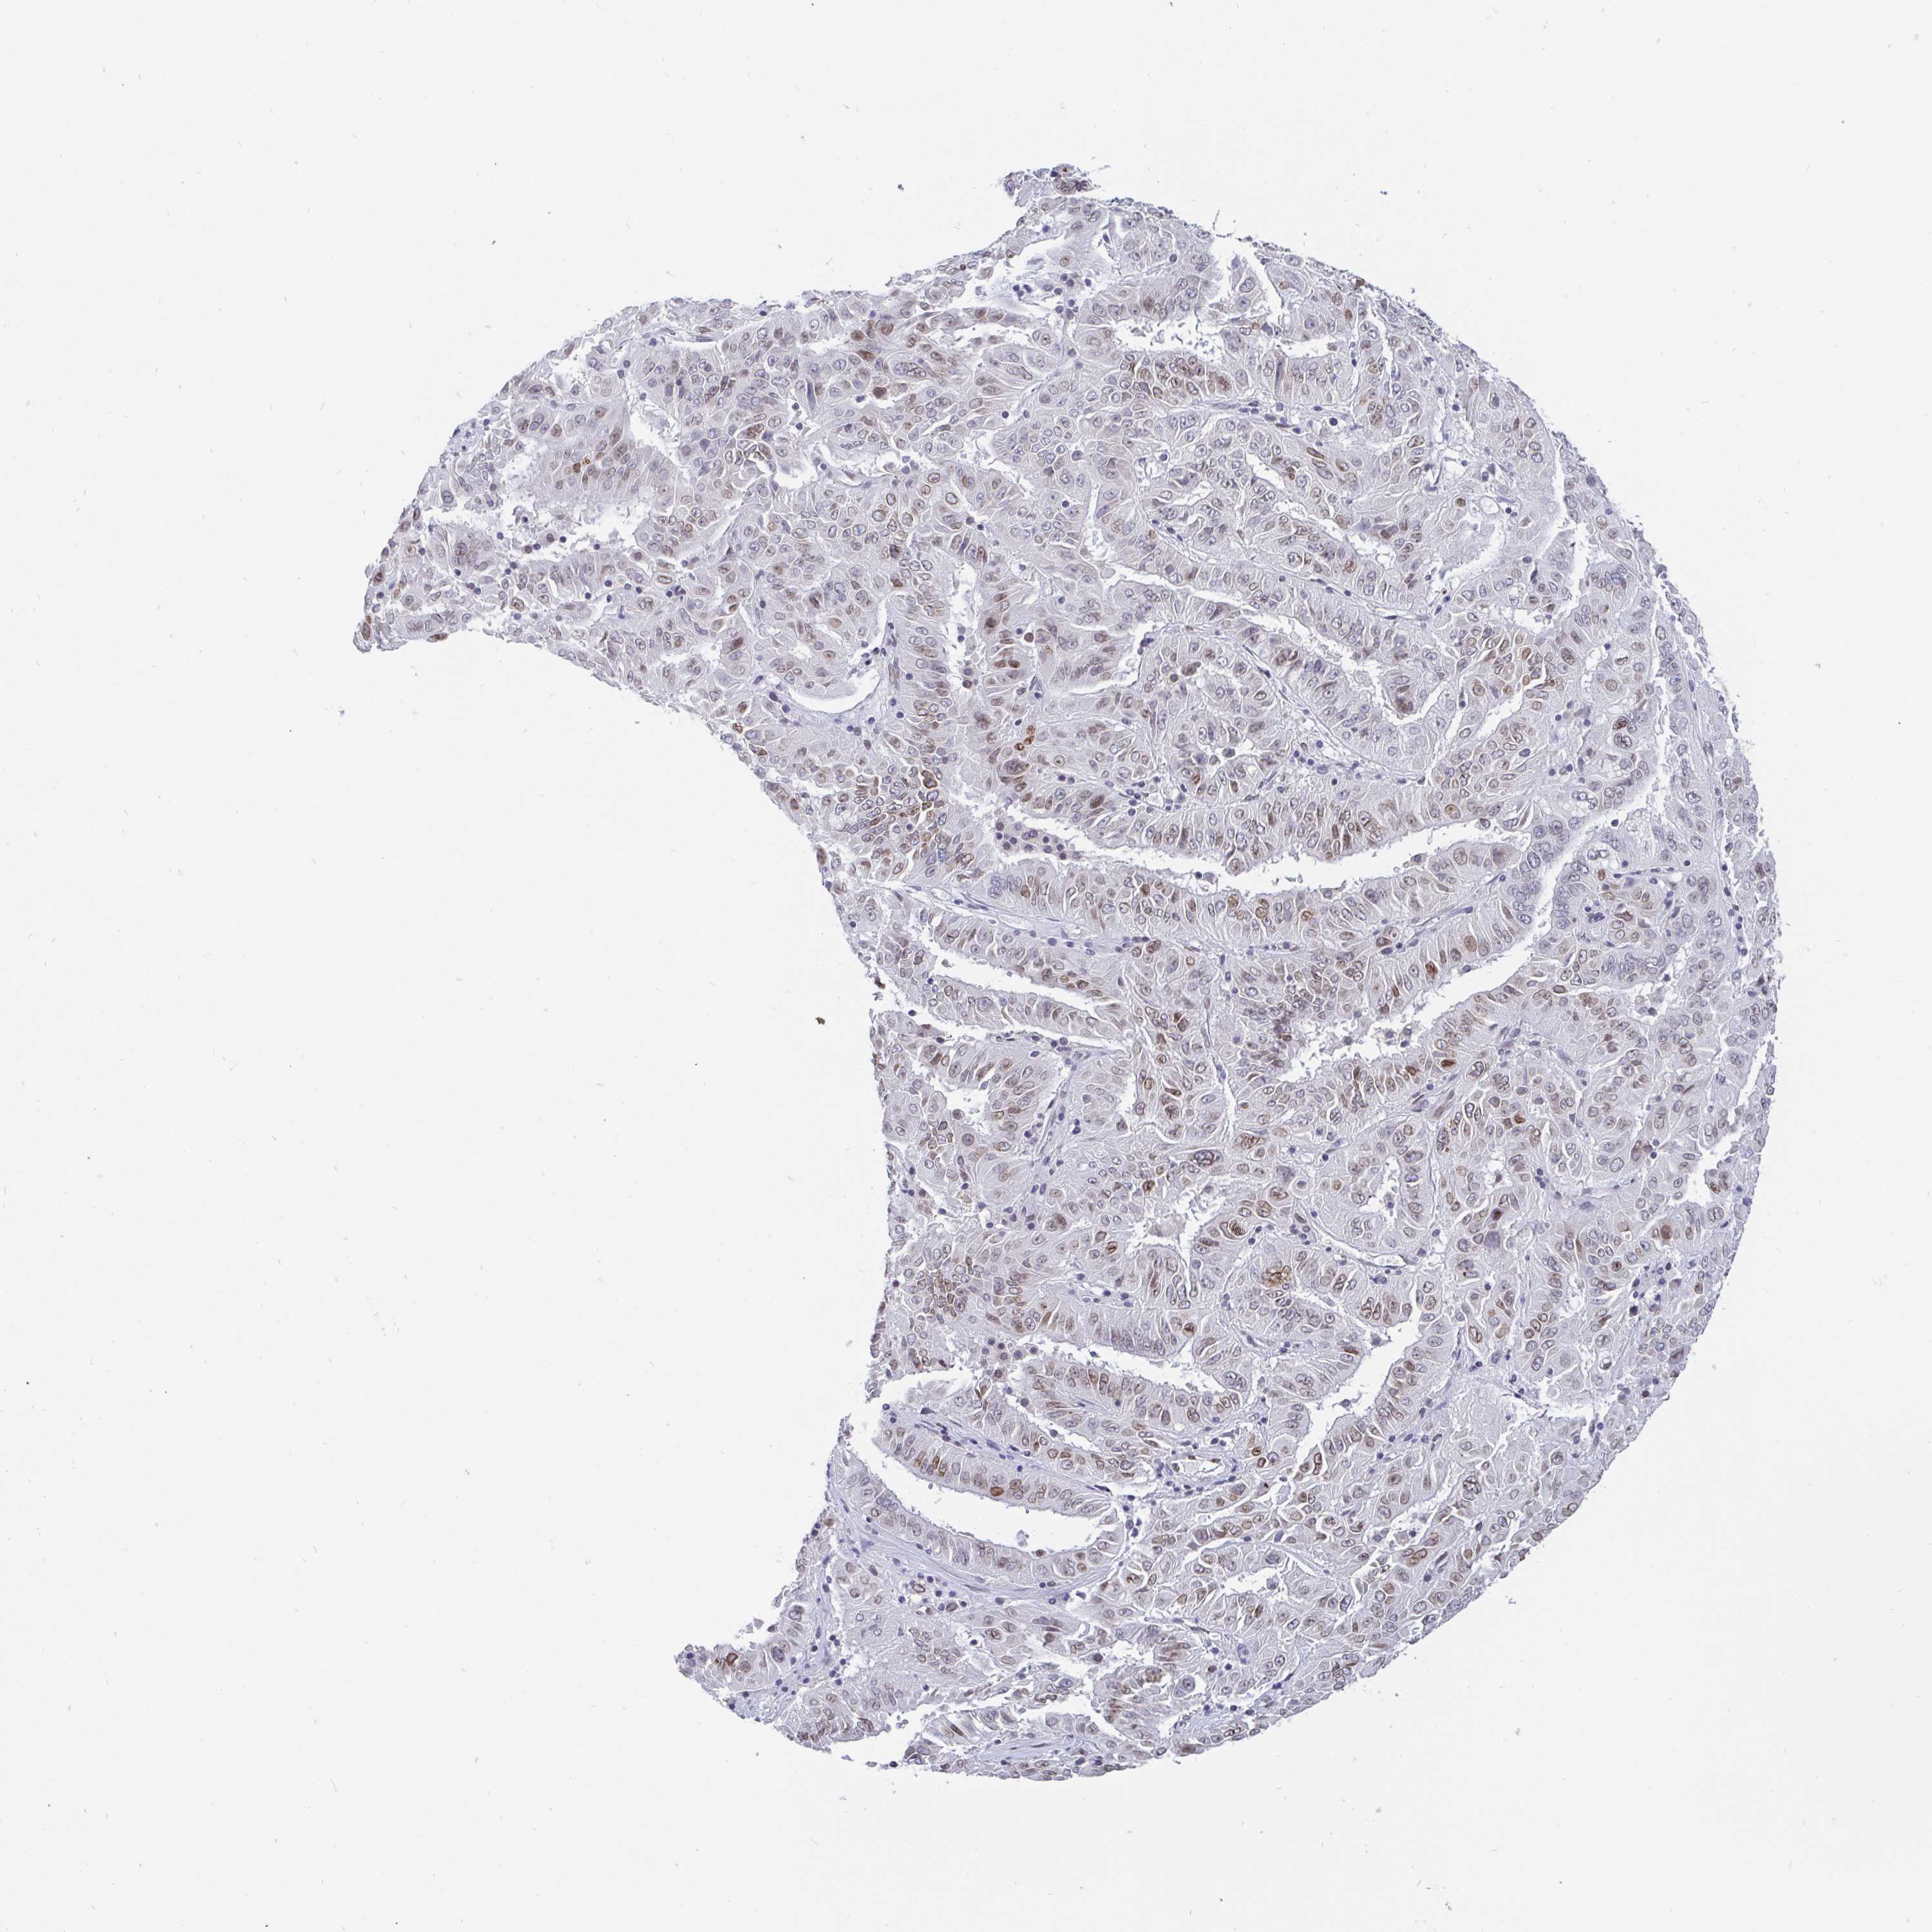

PANCREATIC CANCER - Protein expressioni

A mouse-over function shows sample information and annotation data. Click on an image to view it in a full screen mode. Samples can be filtered based on level of antibody staining by selecting one or several of the following categories: high, medium, low and not detected. The assay and annotation is described here.

Note that samples used for immunohistochemistry by the Human Protein Atlas do not correspond to samples in the TCGA dataset.

Antibody stainingi

Antibody staining in the annotated cell types in the current human tissue is reported as not detected, low, medium, or high, based on conventional immunohistochemistry profiling in selected tissues. This score is based on the combination of the staining intensity and fraction of stained cells.

Each image is clickable and will lead to virtual microscopy that enables deeper exploration of all samples and also displays staining intensity scores, fraction scores and subcellular localization as well as patient and tissue information for each sample.

Staining

High

Medium

Low

Not detected

Intensity

Strong

Moderate

Weak

Negative

Quantity

>75%

75%-25%

<25%

None

Location

Nuclear

Cytoplasmic/membranous

Cytoplasmic/membranous,nuclear

Adenocarcinoma, NOS